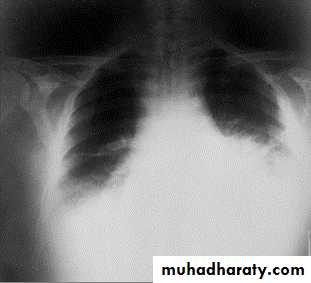

Mediastinal widening and pleural effusion on Chest X-Ray in inhalational anthrax